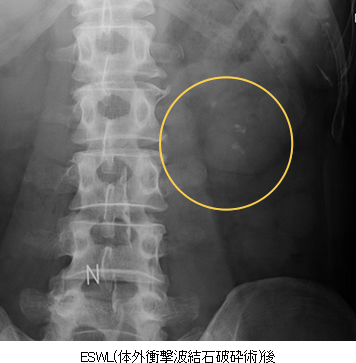

- 結石破砕

- X線とエコーを使って結石に焦点をあわせ、衝撃波で結石を割っていきます。